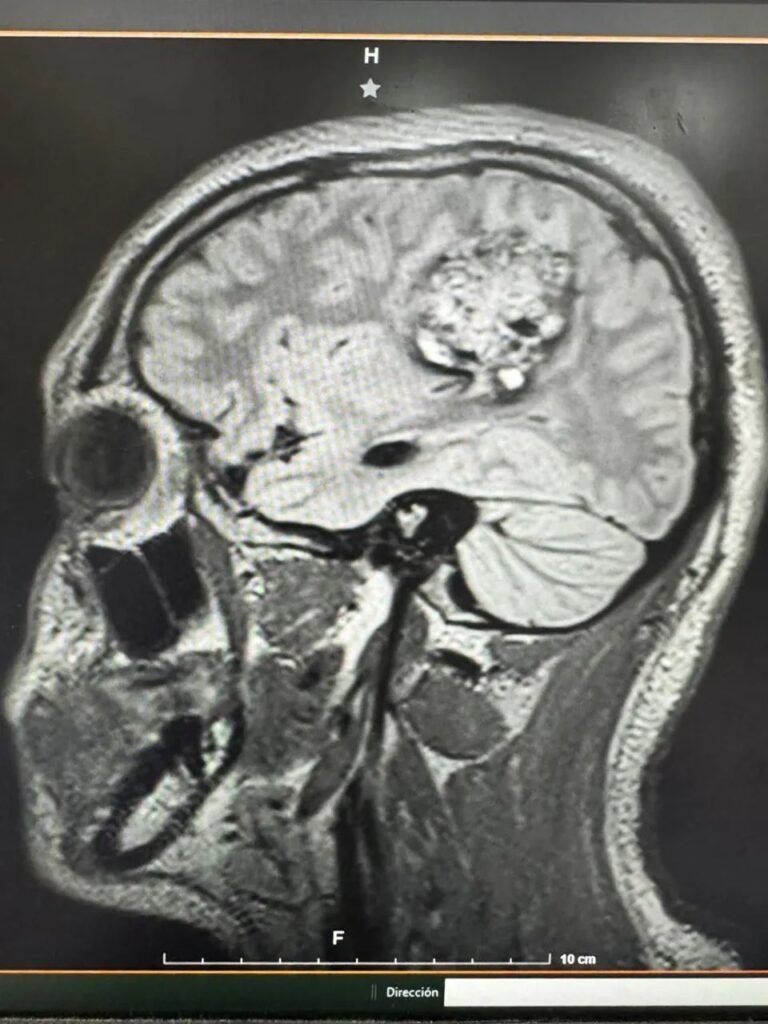

El paciente, de 16 años, presentaba un tumor de aproximadamente cinco centímetros ubicado en una zona delicada del cerebro, cercana a las áreas que controlan el habla y la movilidad. Debido al riesgo de afectar estas funciones, el equipo médico decidió aplicar una cirugía especializada que mantiene al paciente consciente en momentos clave del procedimiento.

Este proceso permitió a los especialistas monitorear en tiempo real las funciones neurológicas del adolescente mientras se retiraba el tumor. De esta manera, los médicos pudieron trabajar con mayor precisión en una región del cerebro considerada de alto riesgo.